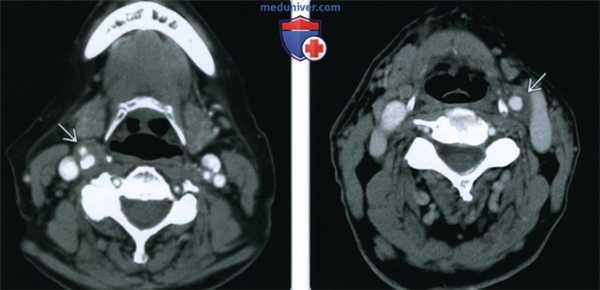

(Слева) КТ с КУ, аксиальная проекция. В области бифуркации правой общей сонной артерии расположено новообразование, равномерно накапливающее контрастное вещество. Опухоль находится между ветвями сонной артерии и смещает внутреннюю яремную вену кзади.

(Справа) КТ с КУ, ранняя артериальная фаза. Опухоль находится в области левой бифуркации и неравномерно накапливает контраст. Она частично заключает в себя сонные артерии, следовательно, относится ко II или III типу по Shamblin. В области правой бифуркации также имеется небольшая параганглиома. Вероятнее всего, заболевание имеет наследственную природу.